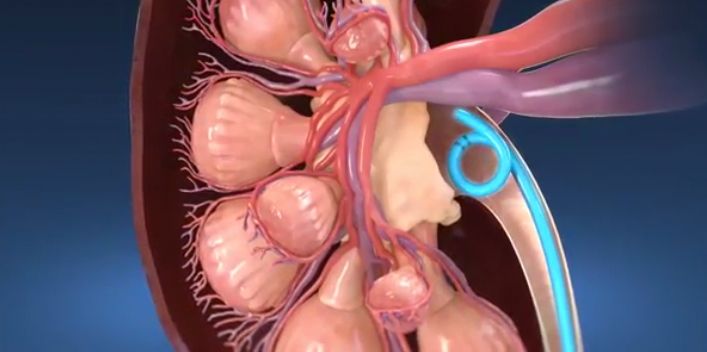

Ureteric Stent Going home Milton Keynes University Hospital new arrivals, Ureteral Stent Placement Memorial Sloan Kettering Cancer Center new arrivals, Ureteric Stent Patient Information Brochures Mater Group new arrivals, Ureteric stenting CIRSE new arrivals, Ureteroscopy and ureteric stenting for ureteric stones Urology new arrivals, Ureteric stent Macmillan Cancer Support new arrivals, IJMS Free Full Text Functional Properties of Polyurethane new arrivals, Ureteric Stent Insertion VIRQ new arrivals, Ureteric stent insertion Chelsea and Westminster Hospital NHS new arrivals, Consent Retrograde Ureteric Stent Insertion TeachMeSurgery new arrivals, Having a Ureteral Stent Saint Luke s Health System new arrivals, Ureteral Stents new arrivals, Dr Tim Nathan Urology Insertion and Removal of Ureteric Stents new arrivals, Ureteral stents are flexible tube like devices with holes new arrivals, Ureteral Stent for Parents Nemours KidsHealth new arrivals, Ureteral Stent Placement What is a ureteral stent Urology Austin new arrivals, Ureteral Stents What you need to know new arrivals, What Is Ureteral Stenting Procedure and Recovery new arrivals, Use of cystourethroscopy to remove an indwelling double J ureteral new arrivals, Ureteral Stent My Kidney Stone Boston Scientific new arrivals, Enhance Comfort and Recovery with Ureteric Stents new arrivals, Ureteral Stent Keystone Urology Specialists new arrivals, Abdominal X ray Artifacts Renal and ureteric stents new arrivals, What to Expect from a Ureteral Stent Advanced Urology new arrivals, Ureteric Stents new arrivals, Your Guide to Ureteral Stents For Kidney Stones Worst Pain Ever new arrivals, Cystoscopy and Ureteral Stent Placement new arrivals, Determination of urinary prostaglandin E2 as a potential biomarker new arrivals, Nephrostomy and ureteric stenting CIRSE new arrivals, Outcomes of outpatient ureteral stenting without fluoroscopy at new arrivals, Ureteral Stents Boston Scientific new arrivals, Ureteral Stent Placement new arrivals, Surface engineered biomaterials and ureteral stents inhibiting new arrivals, Ureteric Stent Insertion OneWelbeck Men s Health new arrivals, Calcified ureteric stent Radiology Case Radiopaedia new arrivals.